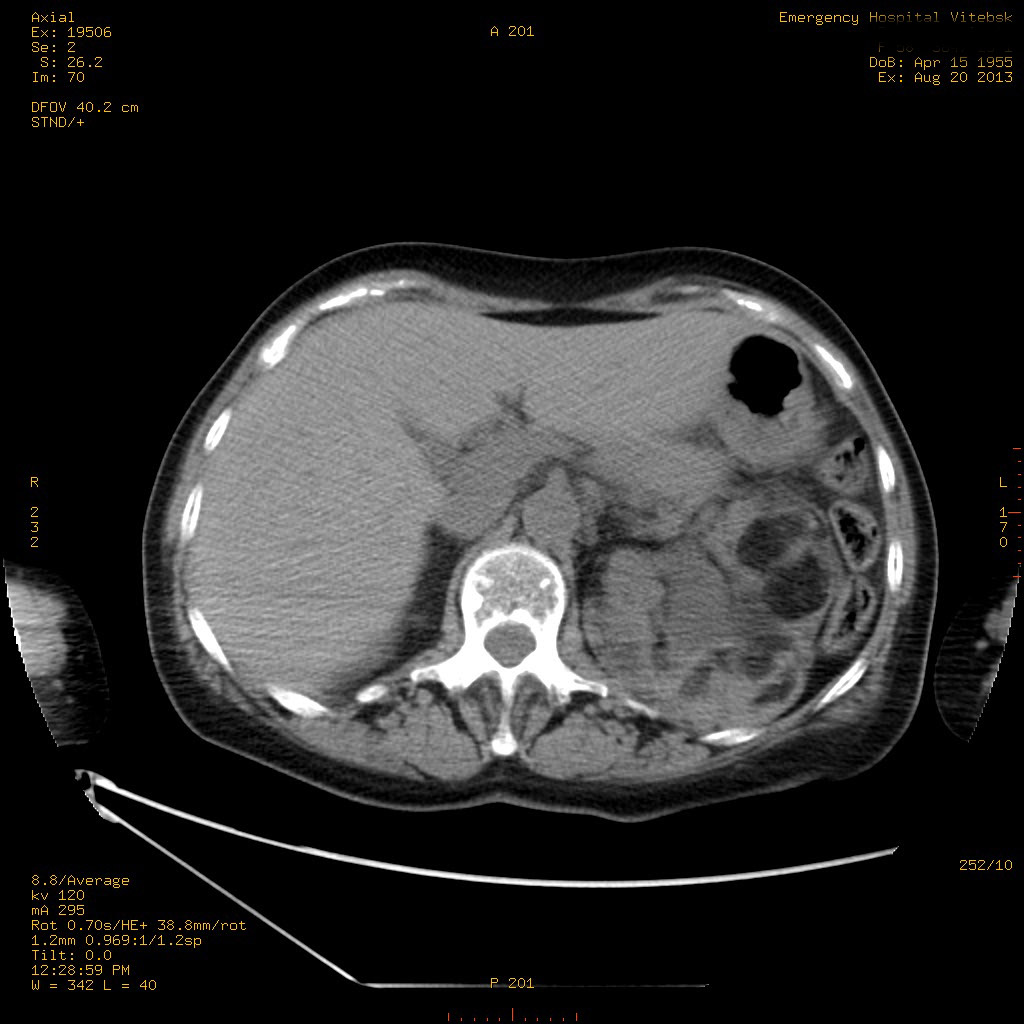

Пожилая женщина с нормальными мочевиной и креатинином.

Ангиомиолипоматоз почек , думаю компонент туберозного склероза.

Да, туберозный склероз.

Случай консультирован на кафедре радиологии Католического университета г.Лёвен (Бельгия) - зав каф. профессор Р.Оуен.